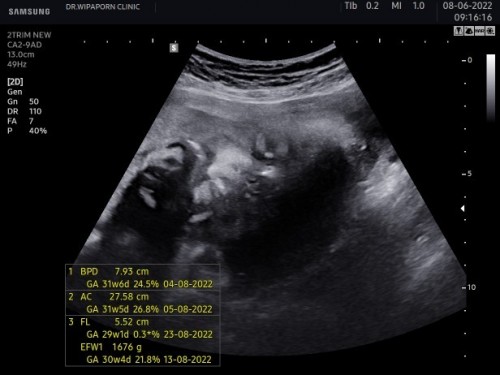

32w+2dทำไมดูหน้าลูกแปลกๆไม่กล้าถามหมอหรือในภาพซาวเป็นแบบนี้คะขอดูรูปลูกๆบ้านอื่นหน่อยค่ะ